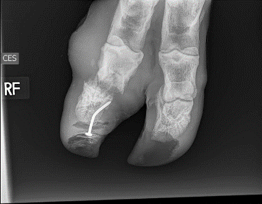

In one case a cow was presented to the VHC that had stepped on a nail, causing a severe lameness. (Figure 7) We completed radiographs to assess how far the nail was imbedded and how much internal damage was present. Soft tissue swelling was extensive. (Figures 8 and 9) There was also a lateral displacement of the third phalanx and a septic coffin joint. (Figure 9) Additionally, an abscess had exited at the coronary band. (Figure 10)

|   |   |   |   |

| Figure 7 | Figure 8 | Figure 9 | Figure 10 |